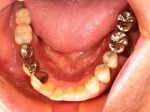

片側2歯欠損片側2歯欠損片側2歯欠損 主訴-入れ歯を使ってみたが違和感強くてダメ。固定のものにしたい。術前下顎口腔内(鏡像) 二次オペ時(鏡像)二次オペ時(鏡像)二次オペ時(鏡像) 術後術後術後、左下奥2本インプラント(鏡像) 術後(レントゲン)術後(レントゲン)術後(レントゲン)、左下奥2本インプラント